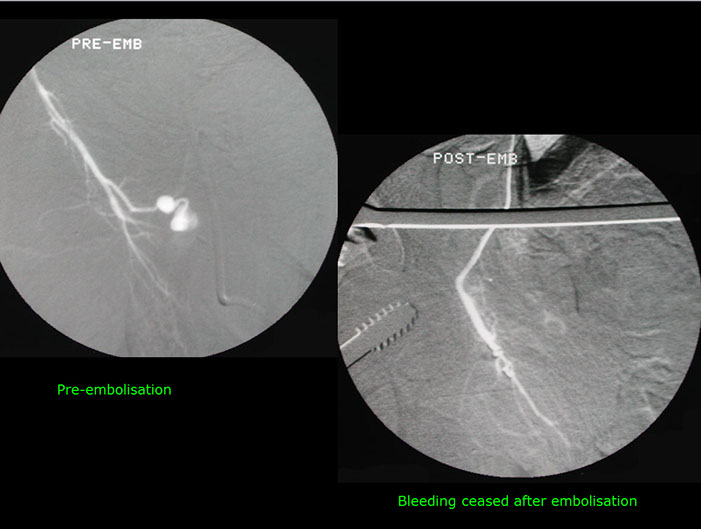

Control of bleeding by embolization.

Bleeding from a pelvic vessel resulting from a fracture, controlled by embolisation